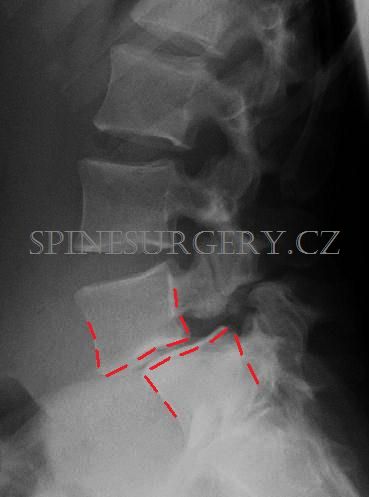

Chronické degenerativní zbytnění meziobratlových fasetových kloubů se nazývá spondyloartróza (Obr. 3). Zvláštním typem postižení páteře, které může způsobovat akutní či chronické obtíže, je spondylolistéza. Jedná se o posun obratle vpřed po obratli pod ním. Existuje několik typů, nejčastěji se vyskytují tzv. istmická a degenerativní. U istmické spondylolistézy (Obr. 4) je posun obratle doprovázen přerušením oblouku obratle- spondylolýzou (Obr. 5) a postihuje typicky segment L5-S1, většinou se jedná pacienty mladšího věku. Etiologie není zcela jasná, podílí se na ní jistě několik faktorů. Při progresi posunu může dojít až k pádu obratlového těla vpřed před páteř- spondyloptózou, často již v dětském, nebo adolescentním věku (Obr. 6), což je doprovázeno závažnými obtížemi. Degenerativní spondylolistéza (Obr. 7) vzniká nejčastěji u starších pacientů, kde dojde typicky v segmentu L4-5 k posunu obratle a k degenerativnímu postižení meziobratlových kloubů- spondyloartróze, což způsobí zúžení páteřního kanálu. Spondylolistézy vzniklé úrazem, nebo tumorozním a zánětlivým postižením jsou vzácné.